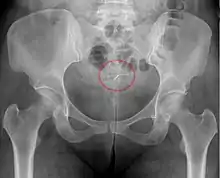

- A "lost coil" occurs when the thread cannot be felt by a woman on routine checking and is not seen on speculum examination.[61] Various thread collector devices or simple forceps may then be used to try to grasp the device through the cervix.[62] In the rare cases when this is unsuccessful, an ultrasound scan may be arranged to check the position of the coil and exclude its perforation through into the abdominal cavity or its unrecognised previous expulsion.